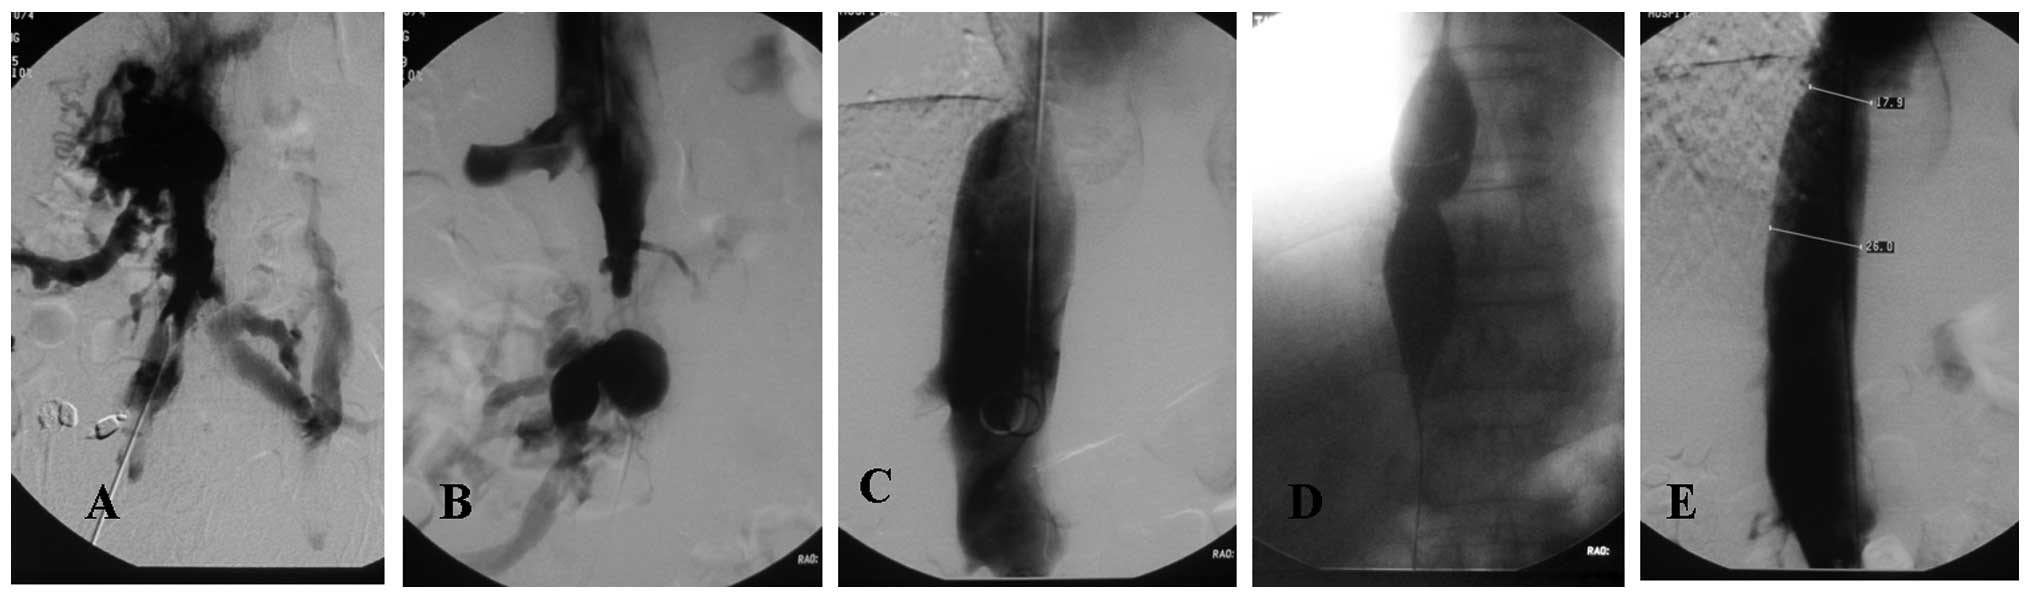

Frontiers | Maternal immune activation as an epidemiological, Treatment of Budd-Chiari syndrome with inferior vena cava,

Treatment of Budd-Chiari syndrome with inferior vena cava, PDF) Racial and Ethnic Disparities in the Impact of Obesity,